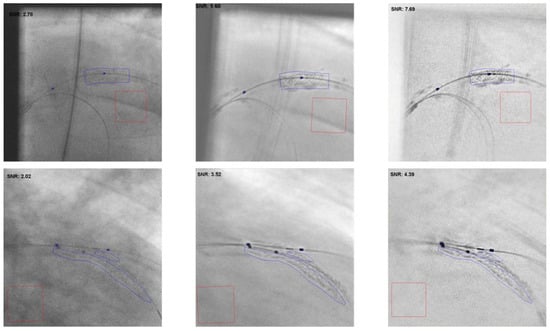

3.2. ESI Image Quality Evaluation

3.3. Signal-to-Noise Ratio